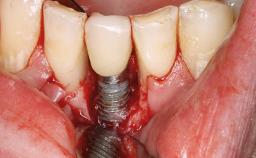

Peripheral Giant-cell Granuloma Associated with Peri-implant Tissues

Giant-cell granulomas (GCG) of the jaws are benign reactive lesions of unknown etiology, unrelated to giant-cell tumors (osteoclastomas), which are defined as benign but locally destructive and aggressive neoplasms (Jundt and coworkers 2005). Depending on their localization at the initial diagnosis, GCG are dived into central (CGCG) and peripheral (PGCG) types. CGCGs occur within the jawbones and appear as unilocular or multilocular radiolucent lesions. The incidence in the general population is very low. They are more commonly found in the mandible, mainly in children and young adults—patients are generally younger than 30 years—and have a greater incidence in females (Heithersay and coworkers 2002). The clinical behavior of CGCGs varies from slowly growing asymptomatic swellings to aggressive lesions that may result in pain, cortical perforation of the affected jaw site, and root resorption (de Lange and coworkers 2007).